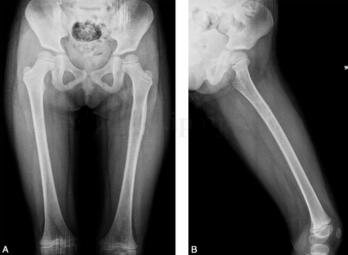

女,5岁,左下肢疼痛月余,近日加重,左下肢活动受限。病来无发热盗汗,无结核接触史。查体:左大腿肿胀,皮温略高,有压痛(图1、图2)。

图1 DR:左股骨上段略膨胀,局部骨皮质略增厚,其内可见小斑点状密度减低区,邻近软组织密度略增高